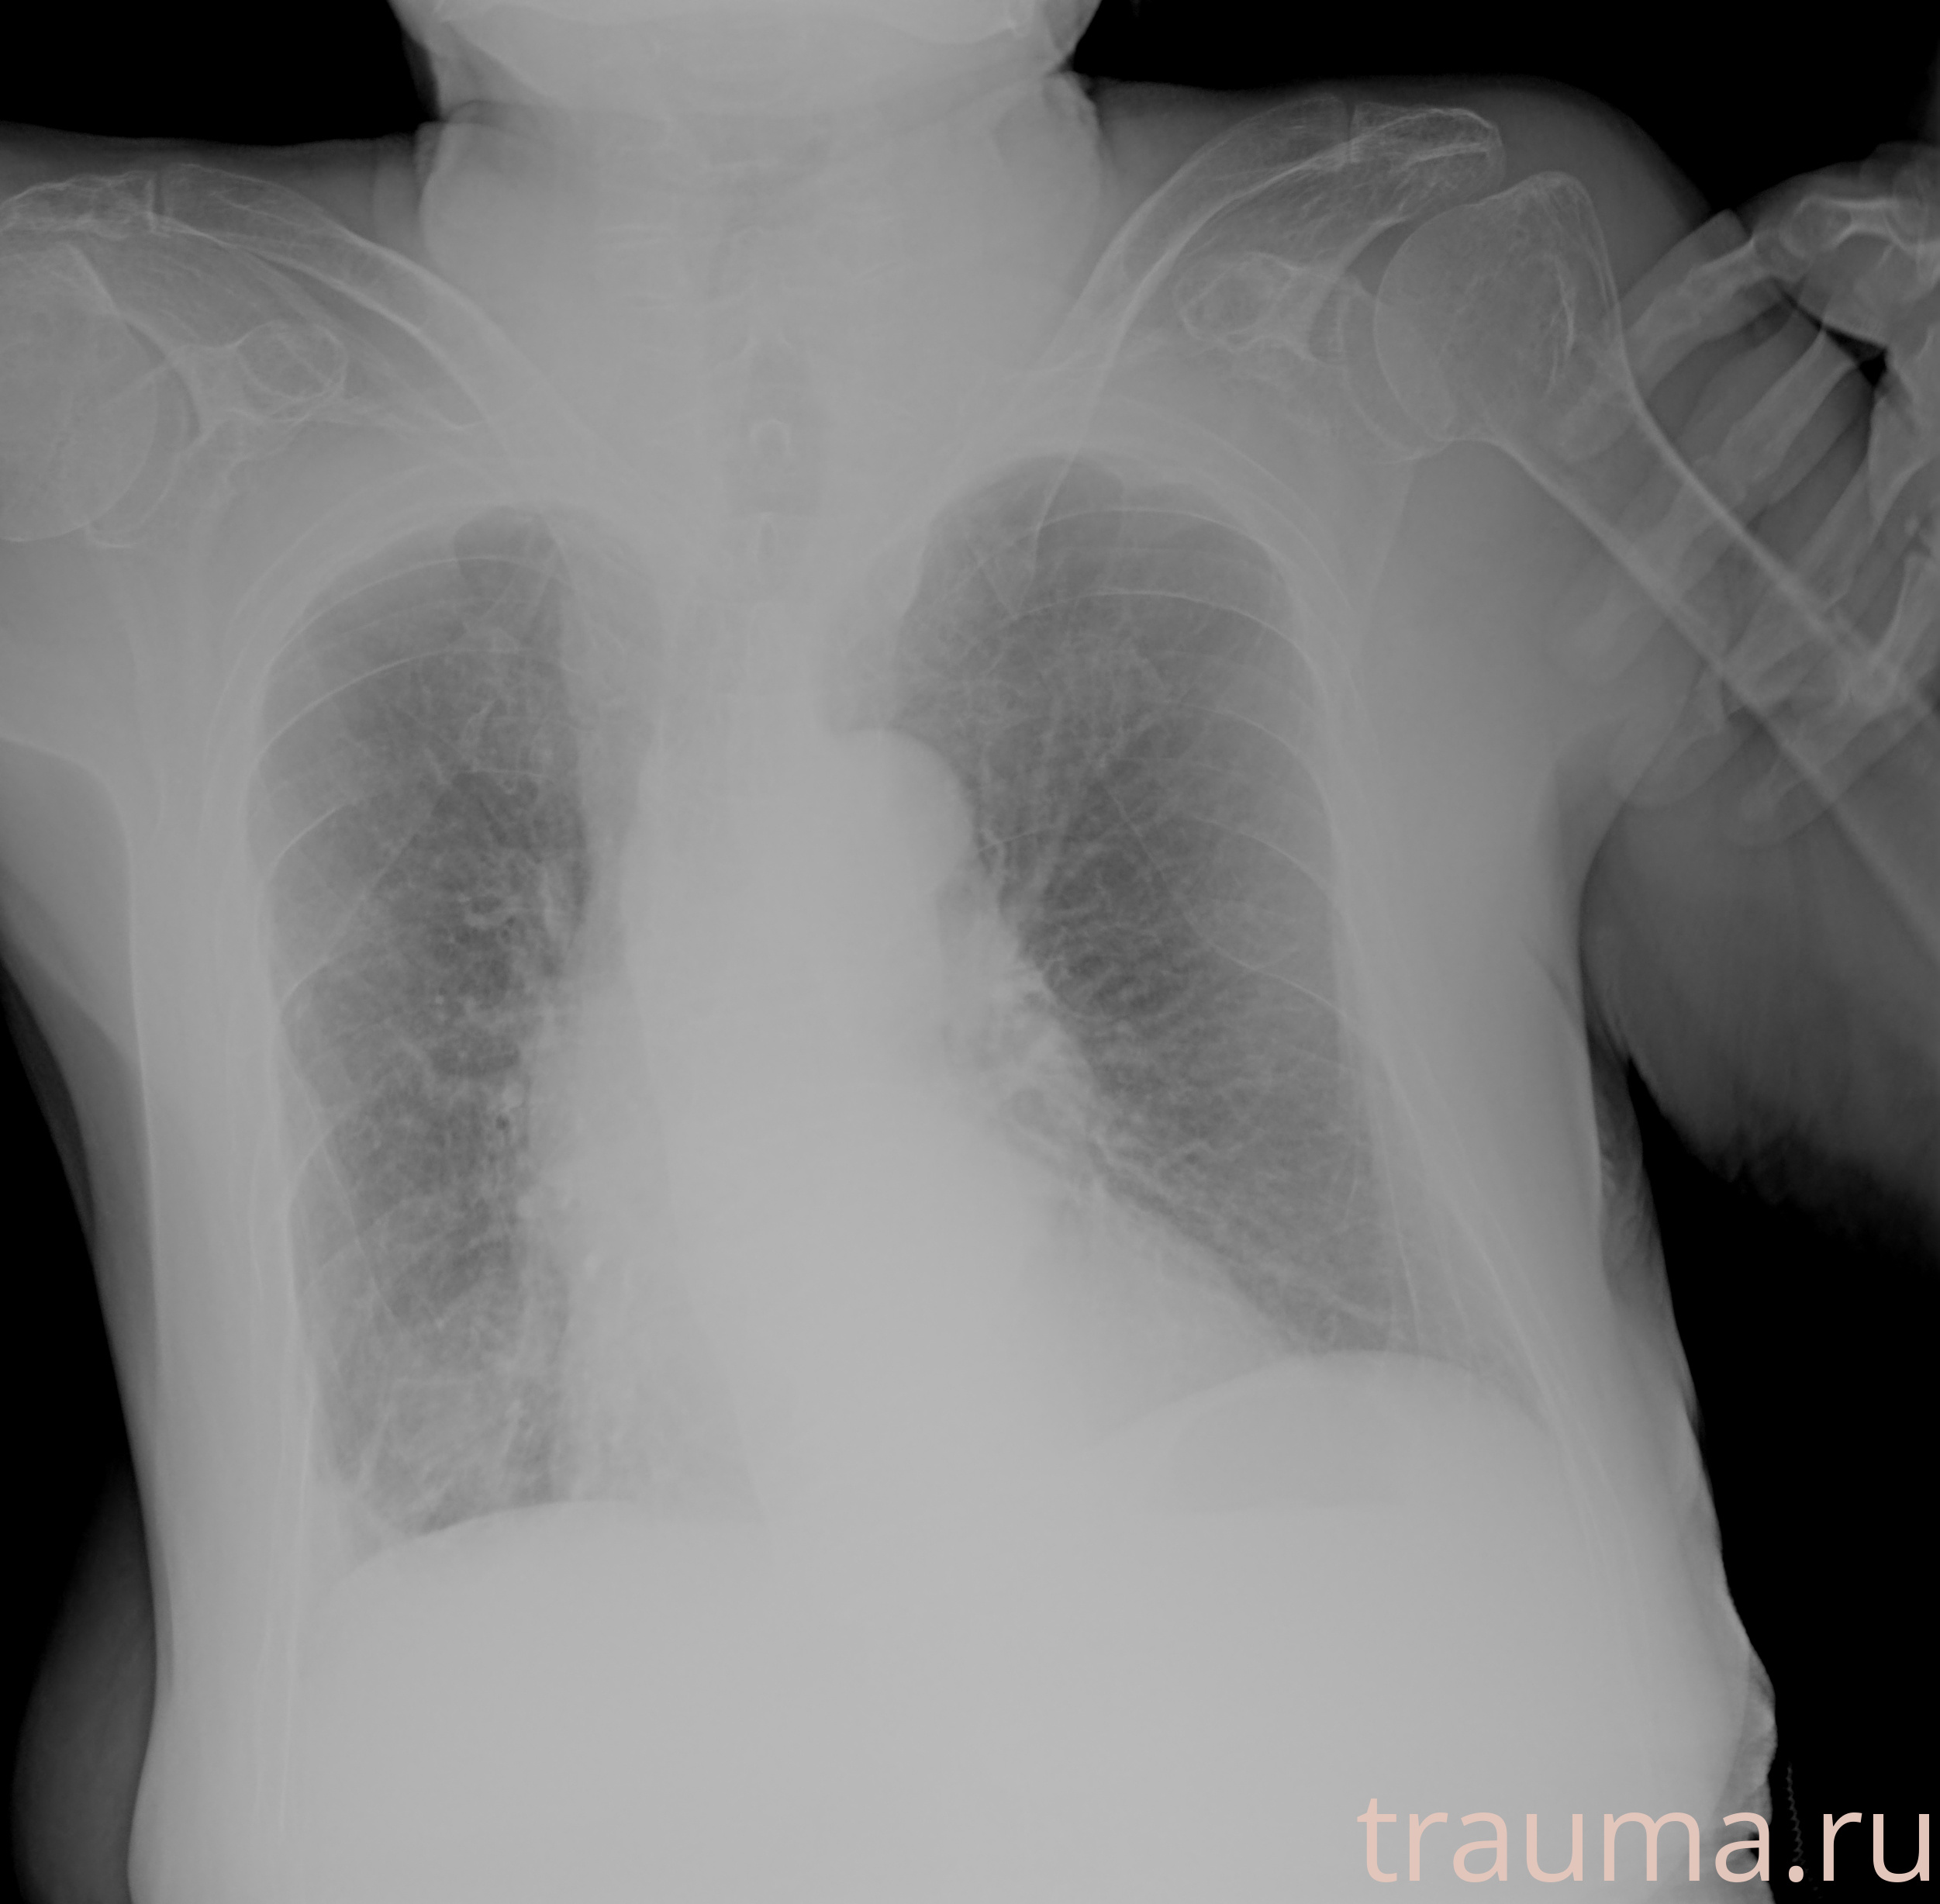

Рентгенограммы

Рентген на дому: по вашему адресу приезжает врач-рентгенолог, травматолог-ортопед с мобильным рентгеновским аппаратом, проводит диагностику травмы или заболевания, делает необходимые рентгенограммы, дает рекомендации по дальнейшему лечению. Получить качественные снимки в домашних условиях возможно благодаря уникальной методике, разработанной МосРентген Центром для института  Склифосовского

при переломе шейки бедра и пневмонии от компании МосРентген Центр - партнера Института имени Склифосовского